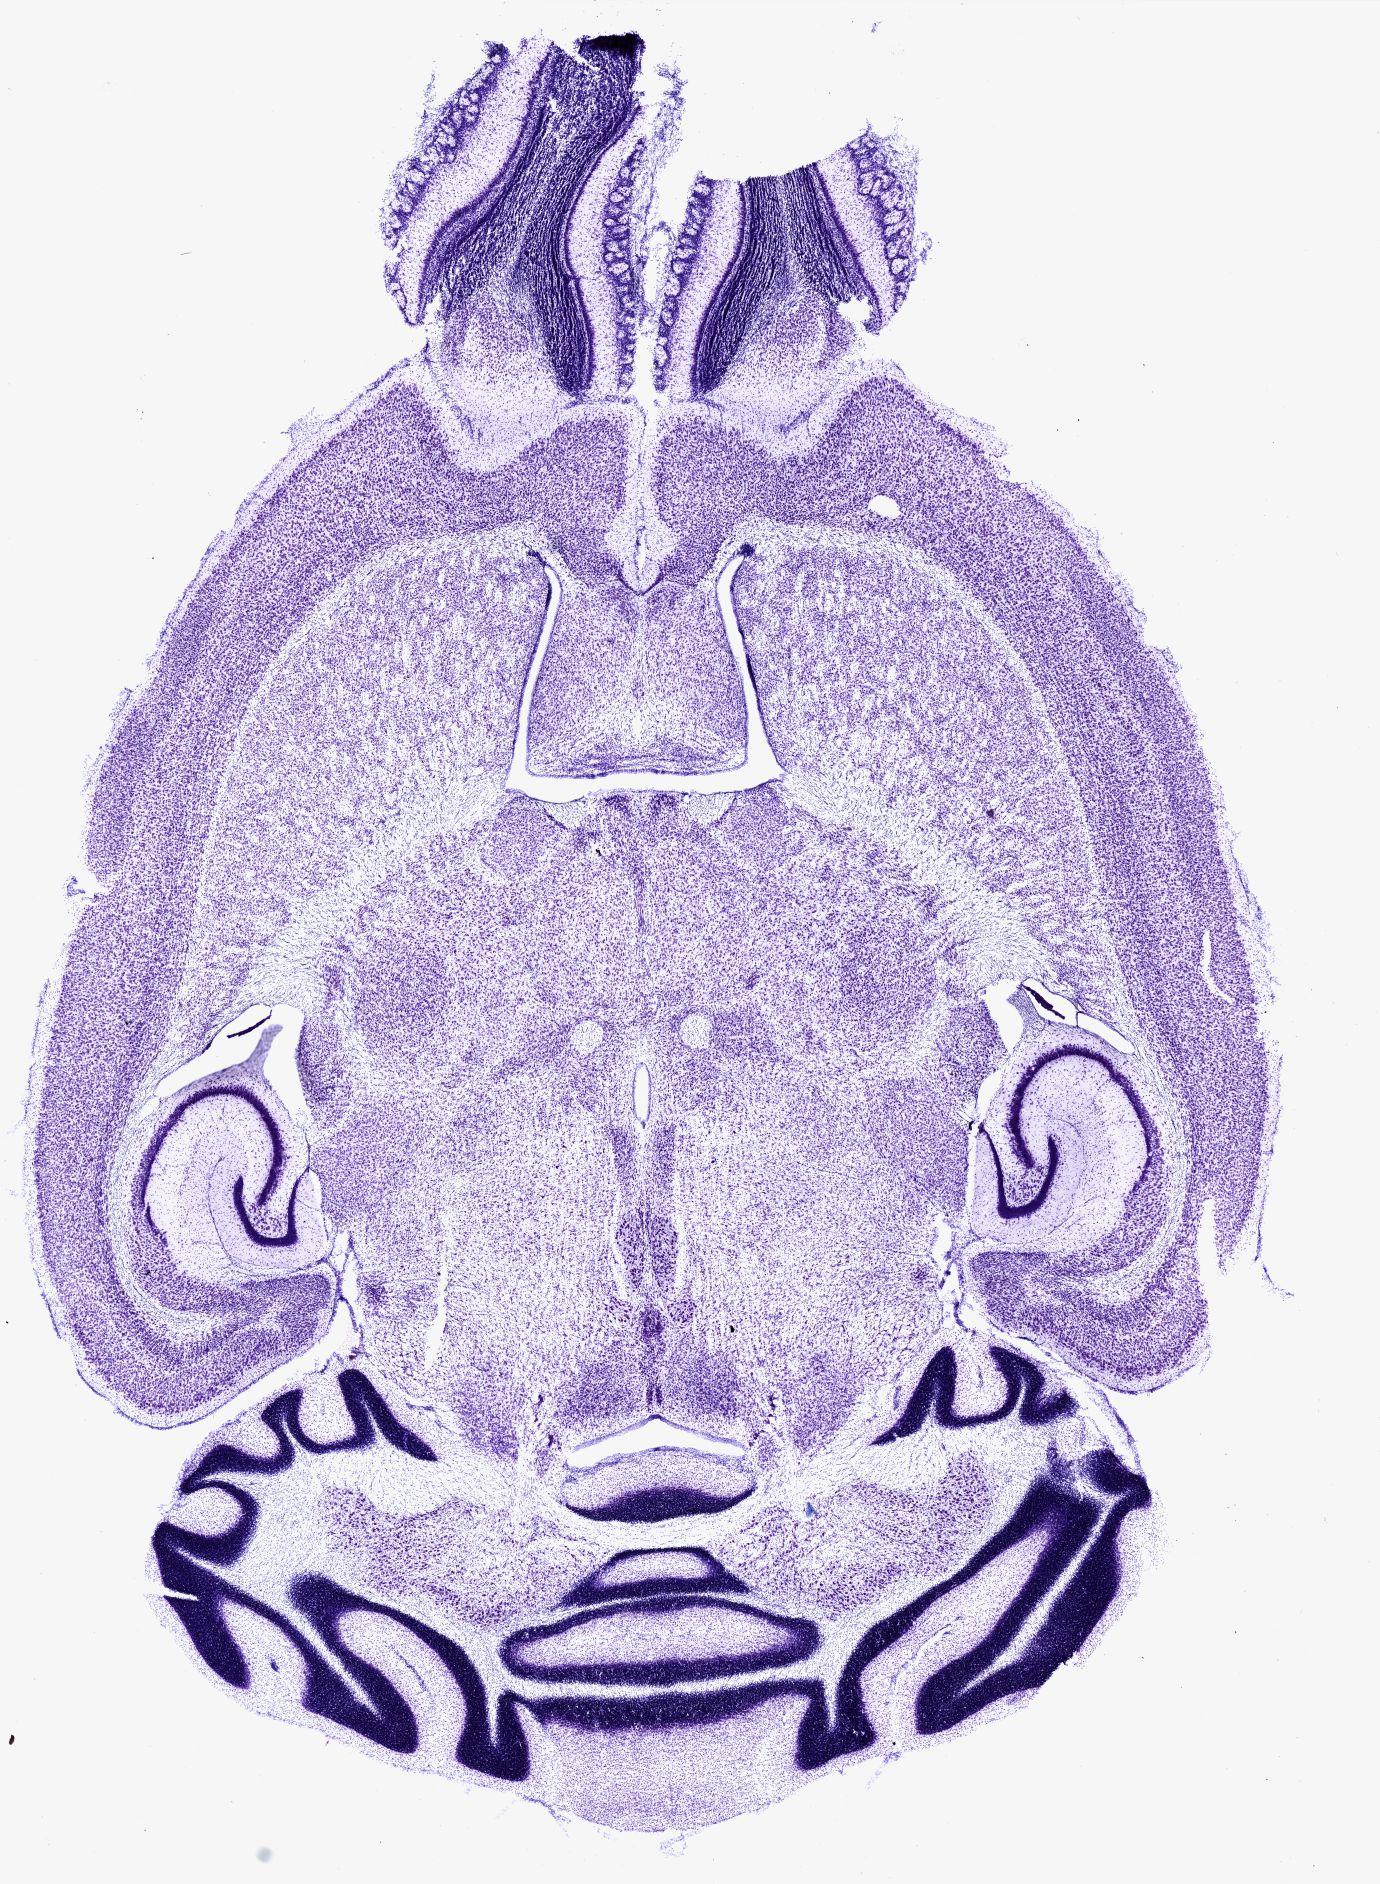

Datasets -> Mus Musculus -> Nissl, horizontal, histo, Whole-Brain, adult

[ Metadata ]   ·   Source: Shawn Mikula